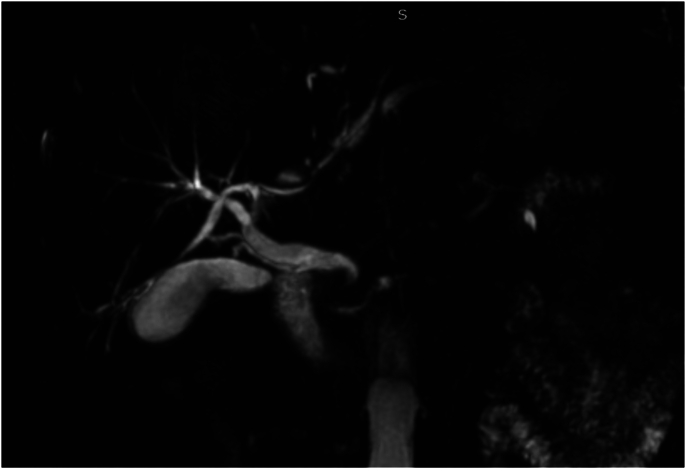

A 63-year-old patient, with no medical history, presented to the emergency department with recent jaundice, and vomiting. Physical examination showed fever and tenderness in the right hypochondrium with no palpable mass. Laboratory tests showed a CRP at 78 mg/l associated with conjugated hyperbilirubinemia at 40 umol/l. Alkaline phosphatase was elevated at 808 UI/l and YGT was elevated at 449 UI/l. Abdominal ultrasound revealed a dilated CBD at 12 mm, with visibility of intrahepatic ducts. Cholangio-MRI found a stricture in the distal common bile duct with multiple hepatic lesions which could be abscesses or secondary lesions (Fig. 1).

The diagnosis of distal CBD cholangiocarcinoma was suspected and tumor markers (Ca 19-9 and ACE) were done but were negative. An echo endoscopy was attempted to confirm the malignant nature of the CBD stricture but it was not possible due to a duodenal stenosis. The patient was reinterrogated and revealed a history of ulcer-like abdominal pain that has been ongoing for ten years. Duodenal biopsy was negative for malignant cells but positive for H. pylori bacteria. We reviewed the Cholangio-MRI and we noticed that the CBD had a hook shaped distal portion. Peptic ulcer stenosis complicated with distal CBD retraction and choledochoduodenal fistula was then suspected. Barium study showed normal passage in the small bowel but an unusual passage in the biliary ducts revealing a hook-shaped distal CBD (Fig. 2). The patient was put on proton pump inhibitors and antibiotics with favorable evolution: regression of jaundice and resolution of the abdominal pain and vomiting.